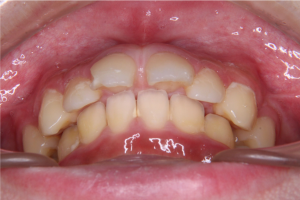

※前歯の噛み合わせ

下の前歯が、上の前歯の歯ぐきに触れそうになるほど深い噛み合わせであることが確認されました。このような噛み合わせは、下あごがやや小さい場合に見られることがあります。